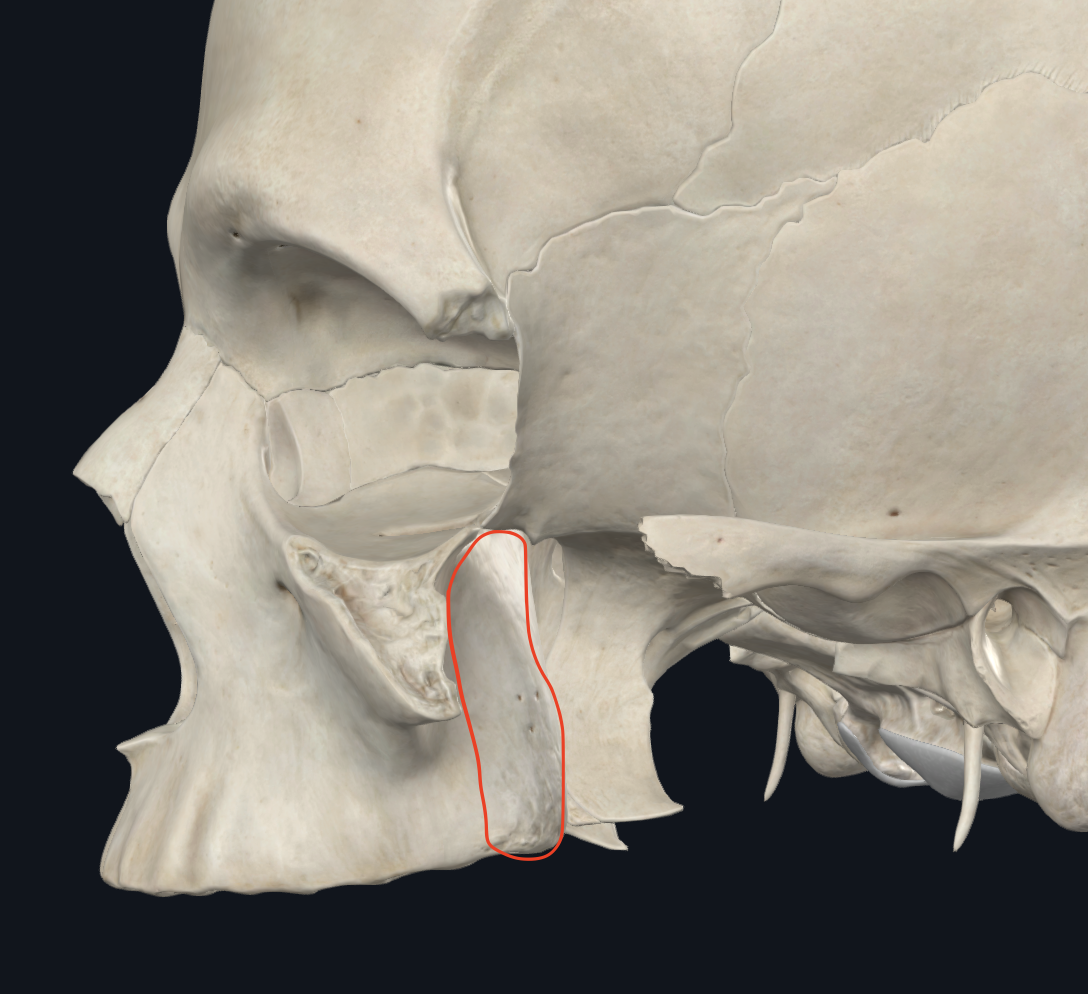

Fosa temporal

Pterion

Nombre de un punto anatomico

Conforma el límite medial(medio) de la fosa temporal

Cresta del frontal, parietal, temporal, y del ala mayor del esfenoides

Fascia del temporal

Límite LATERAL/EXTERNO de la fosa temporal

Conformado por el musculo temporal

Línea temporal superior

Punto de incersión de la fascia temporal

Límite superior y posterior de la fosa temporal

Línea temporal inferior

Punto de incersion del músculo temporal

Límite superior y posterior de la fosa temporal

Límite anterior de la fosa temporal

Límite de la fosa temporal

Superficie posterior del apófisis frontal del cigomático

apófisis cigomática del hueso frontal

Límite inferior de la fosa temporal

Límite de la fosa temporal

Arco cigomático, de forma lateral

Cresta infratemporal del ala mayor del esfenoides, de forma mesial

Imágen es la cresta infratemporal del ala mayor del esfenoides